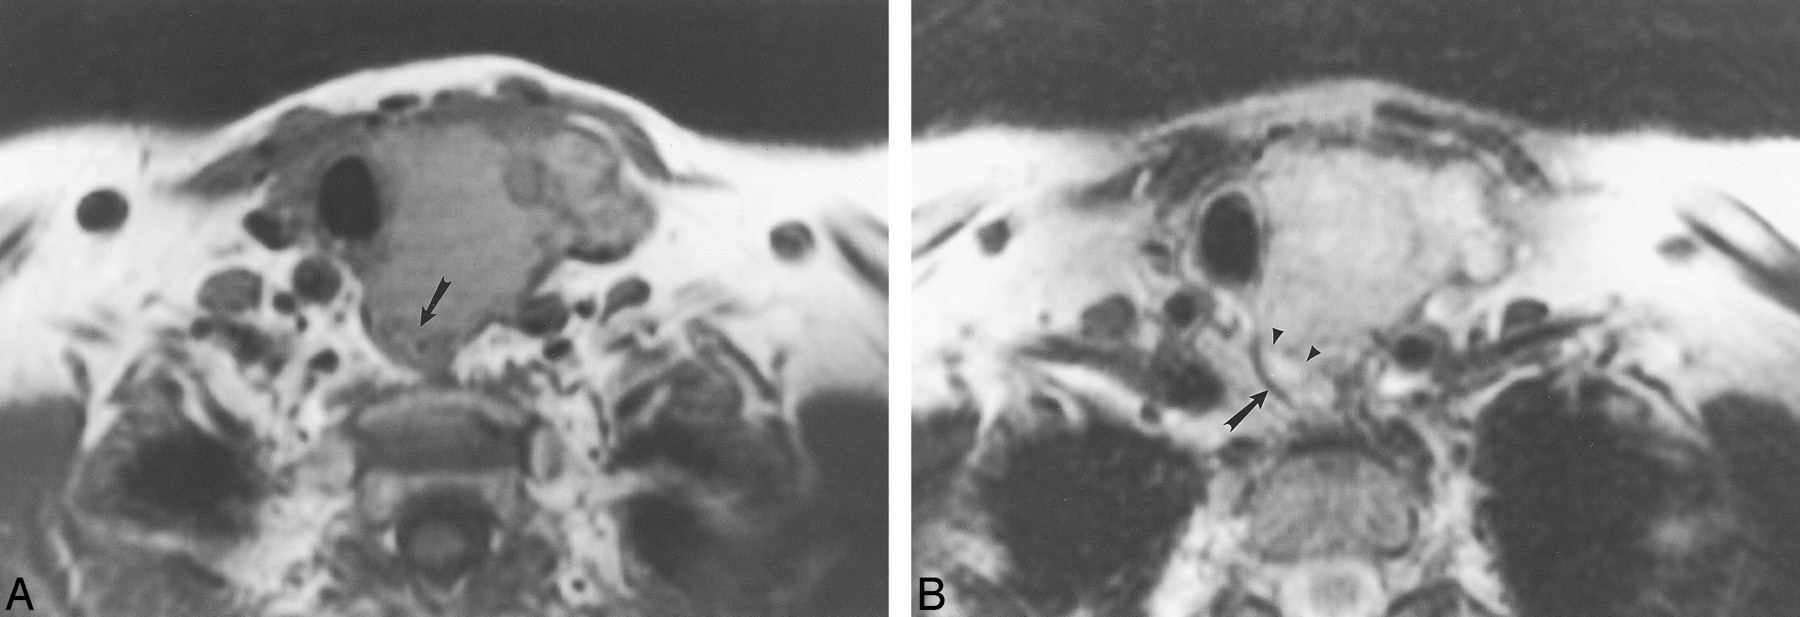

The normal cervical esophagus (Fig 1) shows an intact fat plane and a homogeneously thin wall (less than 5 mm) (13) on MR images, and is isointense to skeletal muscle on T2-weighted imaging (12). The normal esophagus has diffuse enhancement of the mucosa (13). The mucosa of the esophagus is visible on T2-weighted studies (13).

This 68-year-old woman with a benign, left, thyroidal multinodular goiter demonstrates the normal MR imaging appearance of the adjacent esophagus.

A, Axial T1-weighted image (500/16 [TR/TE]) shows an intact fat plane (arrow) between the esophagus and the mass. The thyroid mass is adjacent to the esophagus, and the esophageal lumen is collapsed.

B, Axial T2-weighted image (3500/84) shows normal hypointense signal of the wall musculature of the esophagus (arrow).

C, Axial enhanced 3D FMPSPGR image (220/27; flip angle, 90o) shows mild enhancement of the mucosal lining of the esophageal wall (arrow).